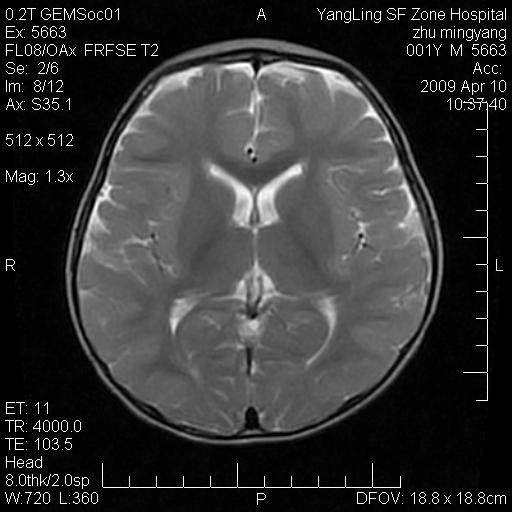

患者:1岁半,两天前外伤收住我院,ct检查小脑占位

考虑星形细胞瘤,建议增强

髓母细胞瘤或血管母细胞瘤,增强后可以鉴别;影像资料见 <。鱼博浪老师的《中枢神经系统ct与mr鉴别诊断》 小脑部肿瘤章节。

髓母细胞瘤或血管母细胞瘤!支持!

支持考虑髓母细胞瘤

考虑----髓母细胞瘤可能性大

考虑髓母细胞瘤或室管膜瘤。

支持髓母细胞瘤。

考虑髓母细胞瘤。

考虑髓母细胞瘤或星形细胞瘤

考虑髓母细胞瘤.

考虑髓母细胞瘤可能性大。

小脑肿瘤.考虑髓母细胞瘤可能.

就病灶部位及临床资料首先考虑髓母.